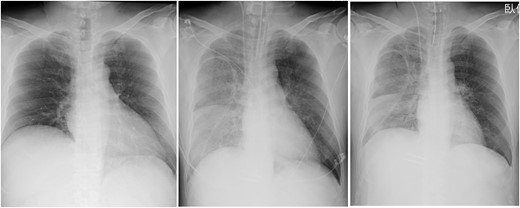

In the intensive care unit, a high positive end-expiratory pressure (PEEP) was required at 12–16 cmH2O, with a peak inspiratory pressure of 30 cmH2O and FIO2 of 1.0. Nonetheless, arterial blood gas showed a pH of 6.99, pO2 of 77.7 mmHg and pCO2 of 107 mmHg. Meanwhile, cardiac function was comparatively maintained, with a cardiac index of ~2.4 l/min/m2. Chest radiography (CXR) showed bilateral consolidation as well as remarkable shrinkage of the cardiac silhouette compared to the preoperative CXR (Fig. 1), suggesting an extremely low left atrial pressure. Therefore, VV-ECMO (Capiox; Terumo Inc, Tokyo, Japan) was immediately initiated after placing a 21 Fr drainage cannula in the right atrium through the right femoral vein and a 15 Fr return cannula through the left femoral vein, guided by ultrasonography. Nafamostat mesilate was used for anticoagulation with a target-activated clotting time (ACT) of 180 s. Within 12 h post-operatively, the patient achieved hemodynamic stability with the administration of catecholamine and fluid replacement, including blood transfusion. The amount of yellowish sputum in the tracheal tube decreased significantly, reaching nearly 4000 ml in total. To compensate for the fluid and protein loss, 14 units (1680 ml) of FFP, 500 ml (100 g) of 20% albumin solution and 3000 ml of crystalloid solutions were intravenously administered over 12 h. No significant bleeding or fluid loss from the surgical site was observed.

Chest radiographs obtained pre-operation (left), post-operation (middle) and 2 days post-operatively (right).

On post-operative day (POD) 2, VV-ECMO was discontinued after noting significant improvement with mechanical ventilation with PEEP at 12 cmH2O and FIO2 at 0.45. The ECMO duration was 39 h. Mechanical ventilatory support was terminated on POD 14. The patient required rehabilitation because of post-intensive care syndrome and was discharged on POD 70.